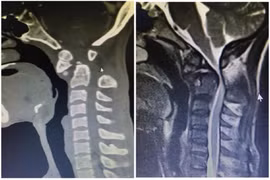

Đắp lá uống thuốc gia truyền trị bướu, ai ngờ bướu thòng xuống cổ, bít đường thở

Bà V.T.H (56 tuổi) có bướu ở cổ từ 20 năm trước. Bác sĩ khuyên bà mổ nhưng bà sợ đụng 'dao kéo' gây nguy hiểm tính mạng nên từ chối và điều trị bằng lá cây, thuốc gia truyền.